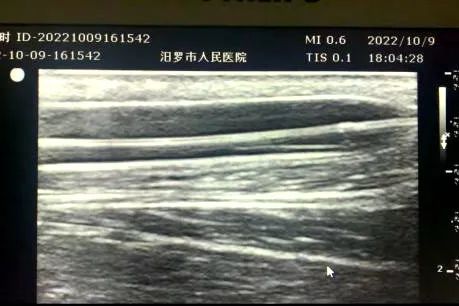

(患者术后内瘘血管明显扩张,血流量增加)

经与家属沟通协商同意后,手术如期进行。超声科聂建胜副主任以彩超进行引导,全科医学科许兴龙主任对该患者失功内瘘行球囊扩张手术,重新开通患者的动静脉内瘘。术后彩超对比提示动静脉内瘘成功再通,血流恢复非常好,左上肢动静脉内瘘血管处触及震颤明显增强,并闻及满意内瘘血管杂音。